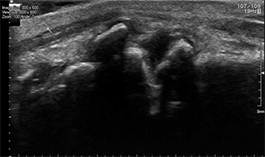

Gewrichtsartrose

Bij gewrichtsartrose slijt het kraakbeen in het gewricht, waardoor de botdelen dichter op elkaar komen te staan en irritatie kan ontstaan. Met echografie kunnen wij veranderingen aan het gewrichtskapsel, de omliggende weefsels en eventuele ontstekingsreacties goed zichtbaar maken. Zo krijgen we een duidelijk beeld van de mate van artrose en welke structuren hierdoor worden beïnvloed.